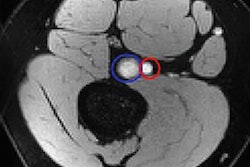

Sonograms and color-coded images of the patellar tendon of a smoker (A) and a nonsmoker (B). The smoker's patellar tendon has a grade 1 (hardest tissue) blue color code, while the nonsmoker's tendon has a grade 3 (intermediate tissue) green color code. Images courtesy of the Journal of Ultrasound in Medicine.In other results, the researchers found weak negative correlations between the smoking amount and patellar tendon thicknesses, as well as strain ratio measurements pertaining to the patellar tendon and the proximal third of the Achilles tendon, Akkaya said.